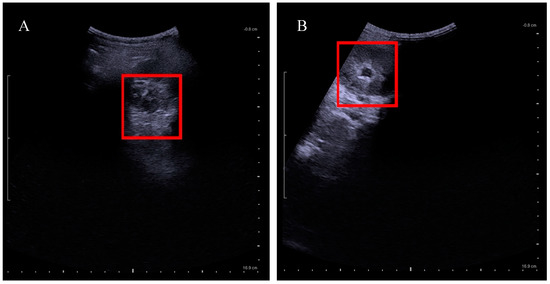

- KUB ultrasound has to be performed one month before and after the untethering surgery. Follow-up appointments are between three and six months depending on urological management